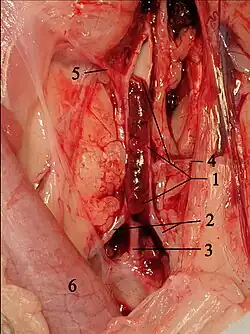

Thrombus in the terminal branch of the aorta in a cat. 1 opened aorta with thrombus, 2 external iliac arteries, 3 common trunk of both internal iliac arteries, 4 circumflex ilium profunda, 5 mesenteric caudal artery, 6 descending colon. circumflexa ilium profunda, 5 A. mesenterica caudalis, 6 Colon descendens

In cats, the blood clots originate mainly in the left atrial auricle.[8] They or parts of them are carried along with the blood flow, enter the aorta via the left ventricle, get stuck at vascular outlets and block them. This condition is called thromboembolism. In cats, this occurs predominantly in the aorta in the area of its terminal branch, i.e., at the outlet of the two external iliac arteries (Aa. iliacae externae). This is also called "saddle thrombus" or "riding thrombus". This results in an ischemia to the rear extremities. In addition, platelets release thromboxane and serotonin, which leads to vasoconstriction and thus to reduced blood flow even to blood vessels that are not directly affected. Serotonin also stimulates nociceptor, which contributes to the high painfulness of the disease.[9] Only in 10% of cases are other blood vessels affected, for example the brachial artery, pulmonary arteries, cerebral circulation, intestinal vessels or coronary arteries.[10][11]